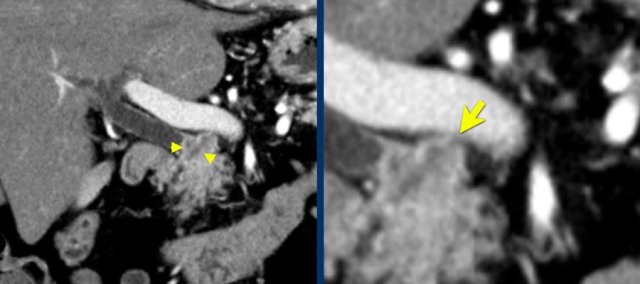

Perineural invasion (2)

The axial image shows a double duct sign (arrowheads).

Although a mass in the pancreatic head is not seen, we must assume that there is a small tumor in the pancreatic head.

On both the axial and coronal images there is extensive soft tissue infiltration from the medial side of the pancreatic head toward the SMA (yellow arrows).

This is a typical pattern of perineural growth.

In this case leading to 90 – 180 degrees contact with the SMA.